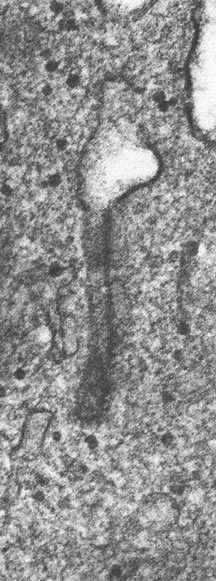

- Birbeck Granules: Electron Microscopy demonstrates granules that often take the form of a tennis raquet and form from complex invaginations of the cell membrane